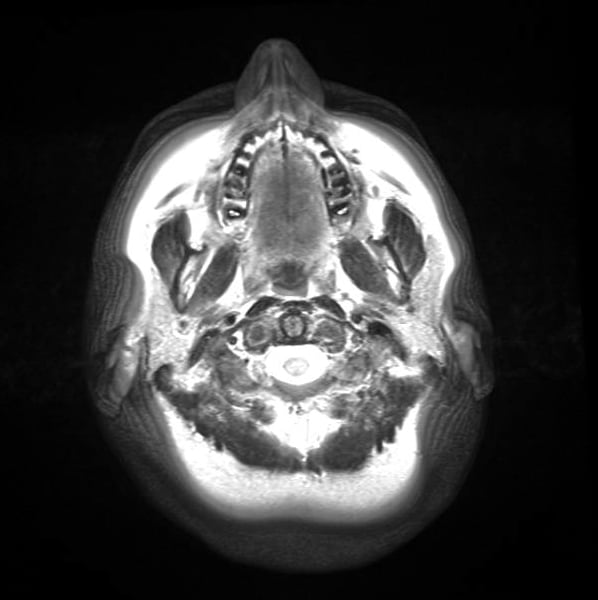

A powerful type of MRI scan releases the toxin from silver-coloured amalgam fillings a study finds. June 27 UPI –When amalgam fillings sometimes referred to as silver fillings are exposed to ultra-high-strength MRI scans they can release toxic mercury according to a new study. I have four silver fillings and have had a brain mri so Ill think youll be fine.

The difference between urinary mercury in the exposed and control group 72 hrs after MRI 96 h after restorationwas significant p0046. These findings provide further support for the noxious effect of MRI exposure to strong magnetic fieldand release of mercury from dental amalgam fillings. High-powered MRI scans may pose a potential poisoning risk to people with silver dental fillings warns new research.

The study shows that ultra-high-strength 7-Tesla MRI scanners may release. Mercury is a powerful neurotoxin and at certain levels can cause neurological issues auto-immune disease chronic illnesses and mental disorders. Silver fillings consist of 50 mercury along with a combination of silver tin and copper.

Exposure to ultra-high-strength MRI may release toxic mercury from amalgam fillings in teeth according to a new study appearing online in the journal Radiology. The effect was not seen however in the lower strength more commonly used 15 T MRI. Amalgam fillings also known as silver fillings have been a staple of dentistry for many years.